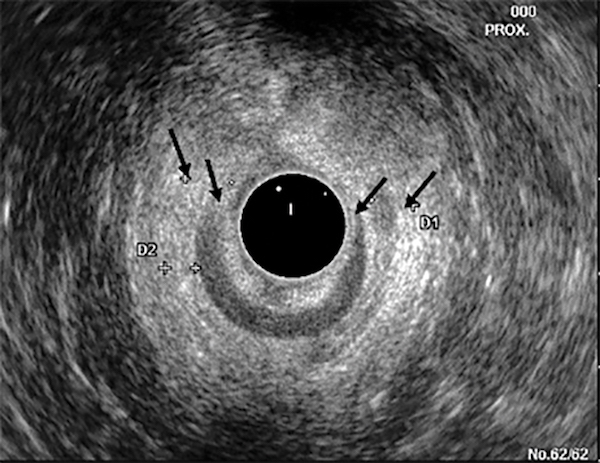

A 55-year-old woman, para 2, without any history of back trauma or injury presents with a 4-year history of progressively worsening fecal incontinence. She cannot sense stool coming out and wets her pants frequently, using 3 pads daily. She had a normal colonoscopy 1 year ago. She denies any bleeding. Her stools are mostly formed (Type 4 on a Bristol stool scale). The patient trialed on psyllium without any relief of her incontinence. To assess this patient further, an anal ultrasound study was performed [FIGURE]. Which of the following findings best describes the anal ultrasound image?

A. Decreased resting and squeeze anal sphincter tone

B. Large external anal sphincter defect but normal internal anal sphincter

C. Normal external anal sphincter but large internal anal sphincter defect

D. Decreased squeeze tone

E. Large external and internal anal sphincter defect